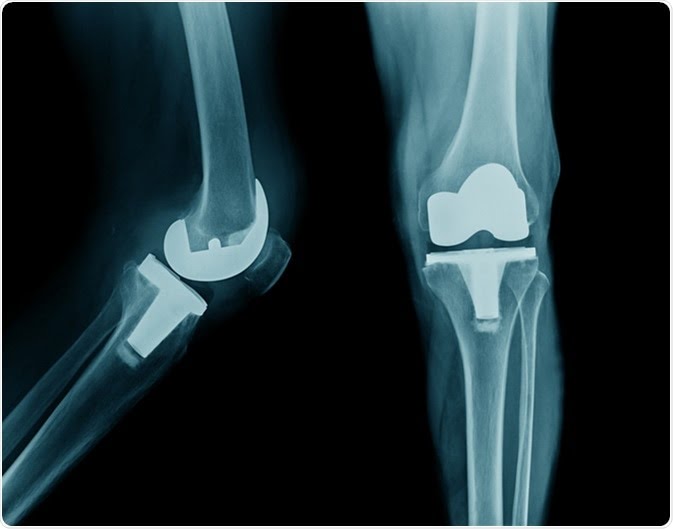

Total knee replacement

KNEE